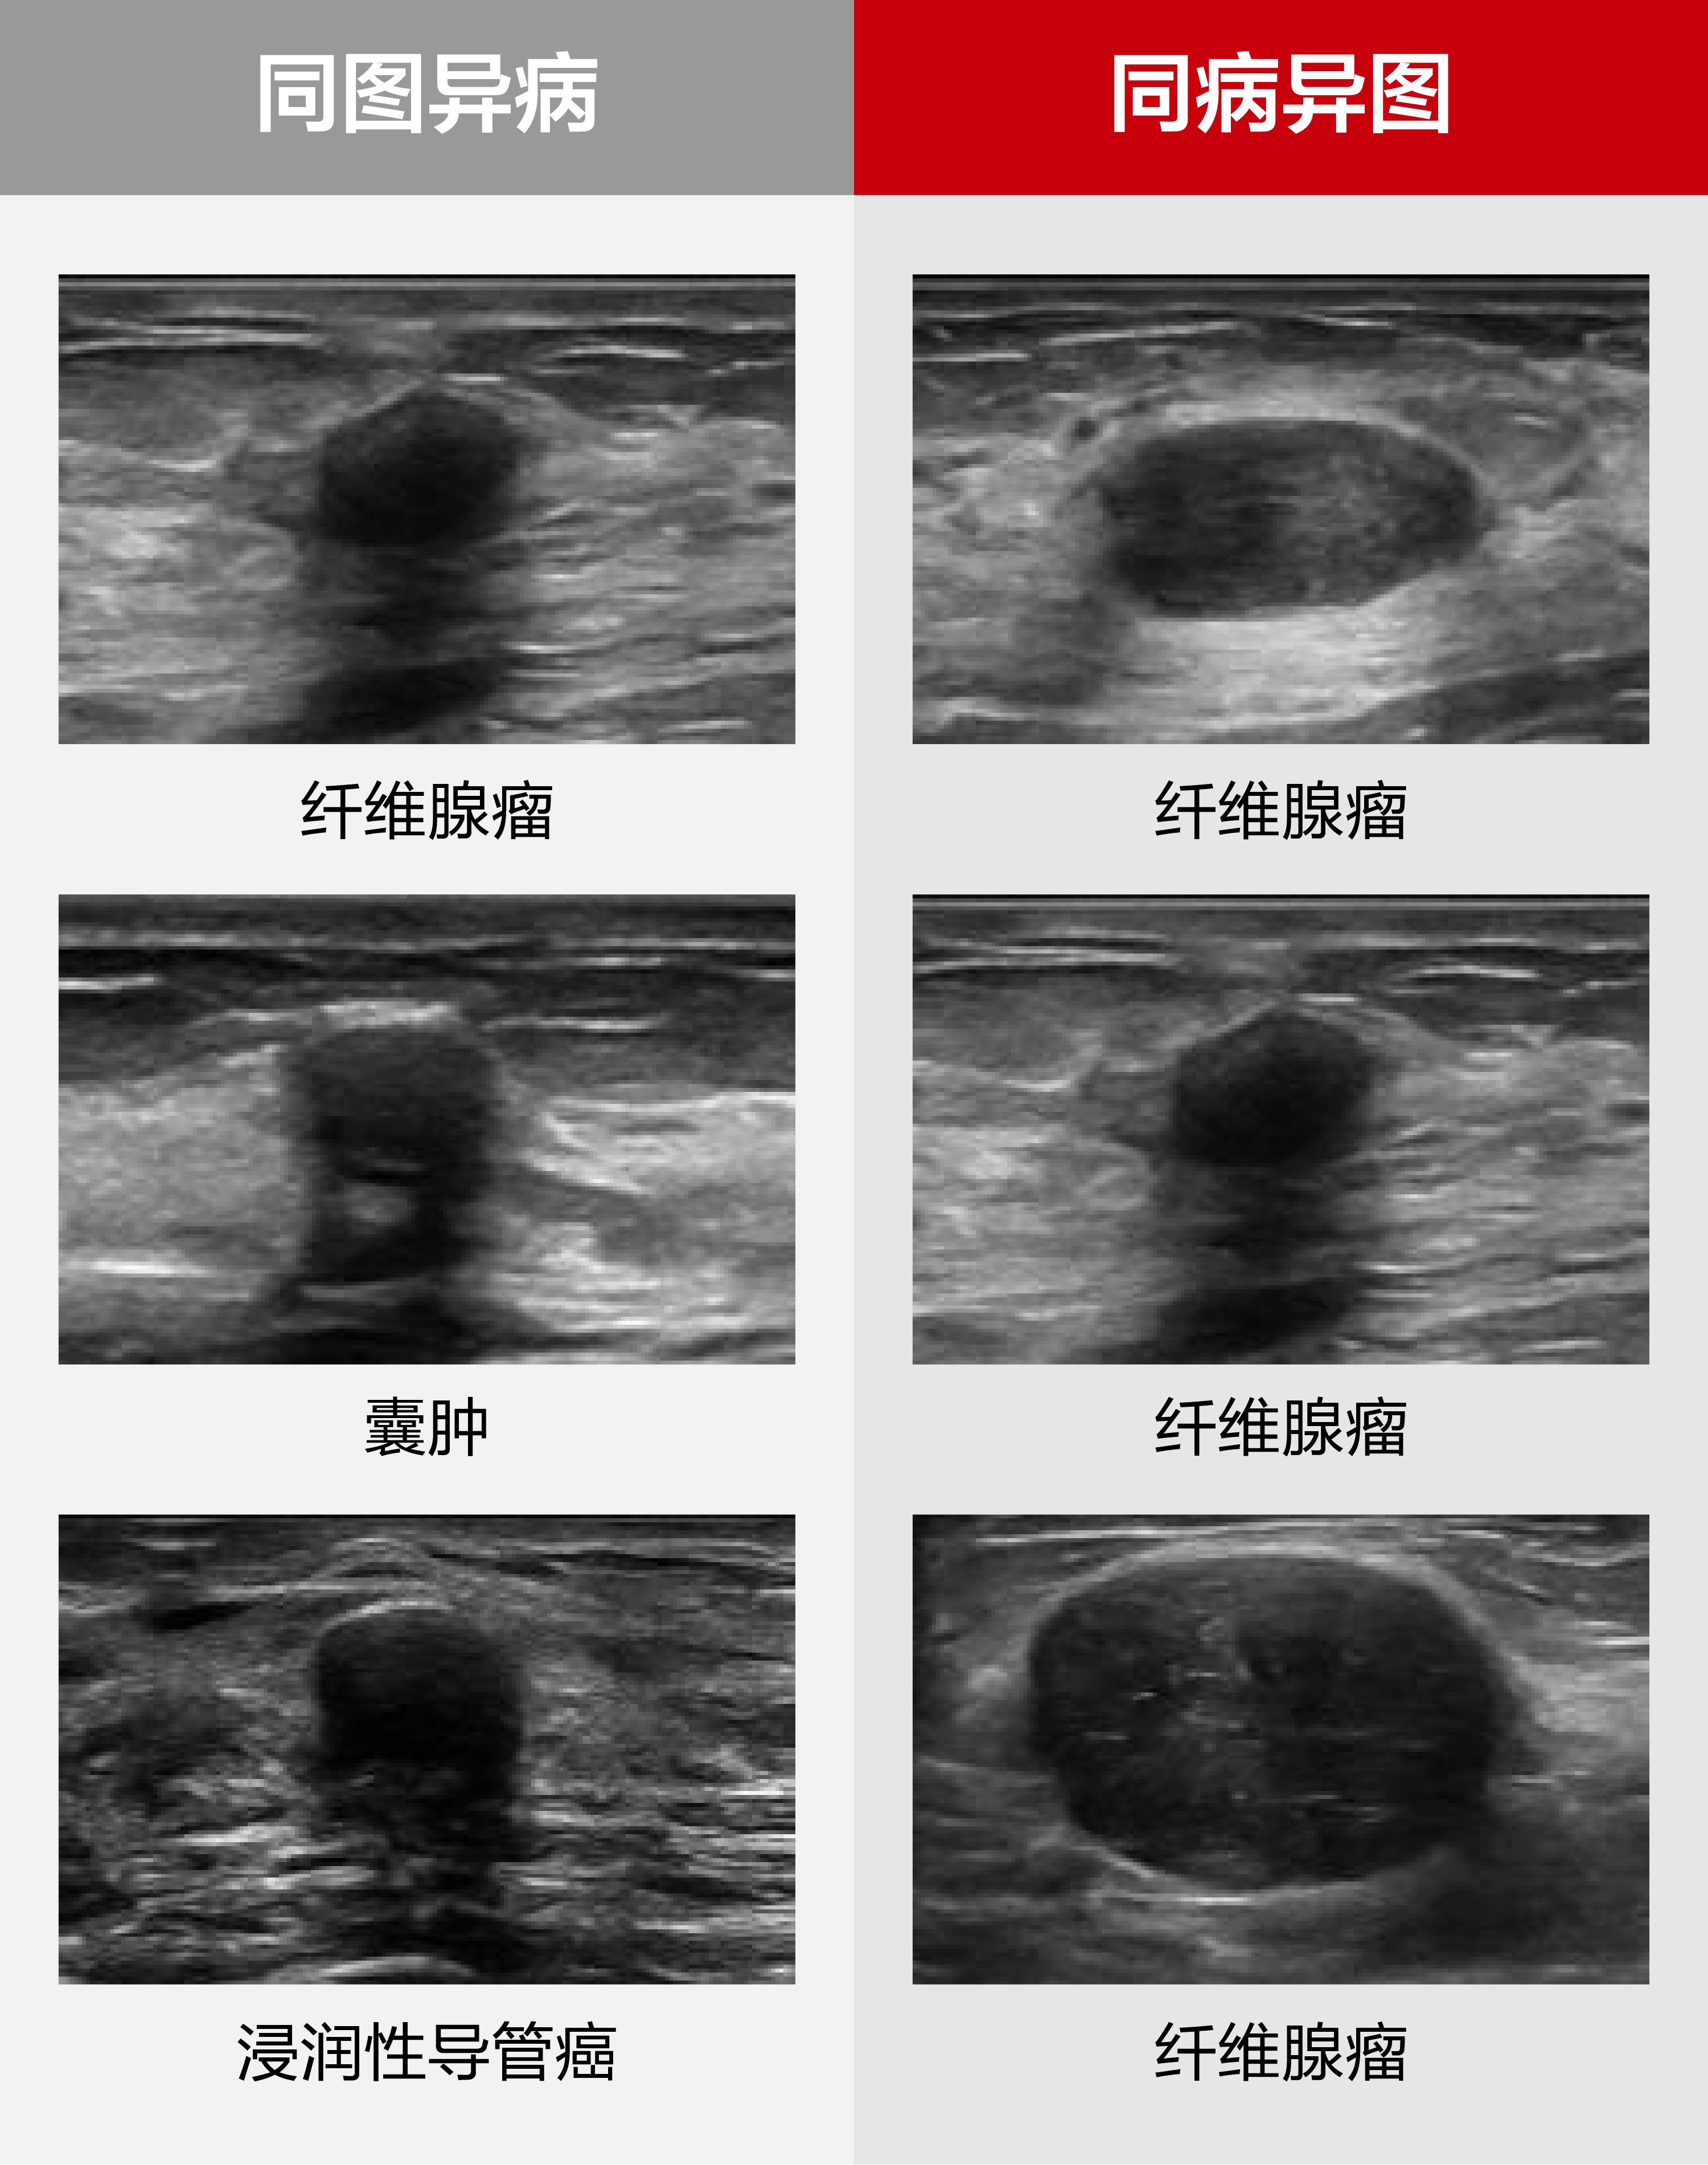

然而,单切面二维图像的局限性、病例表征的非特异性、恶性肿瘤的隐匿表征,以及超声经验积累周期长等问题,成为全球超声医学发展亟待解决的难点。乳腺病灶的精准诊断评估在临床上仍面临巨大挑战,尤其困扰经验较缺乏的年轻超声医生。

为了应对这一挑战,迈瑞以《乳腺疾病超声检查质量控制专家共识(2019版)》为基准,以覆盖实际临床场景的图像与专家组诊断结果,作为训练数据及金标准,通过创新的深度学习算法,将临床知识与高年资医生对图像判读的经验融入辅助诊断模型中,即使面对复杂病变,软件也可以给出高效精准的临床分类诊断。

以临床为导向,迈瑞乳腺超声辅助评估软件具以下创新优势:不改变诊疗操作习惯的多切面综合分析;全自动化分析流程,图像导入后无需人工干预,可以直接得到分析结果;BI-RADS六分类诊断(2类、3类、4A类、4B类、4C类、5类)、BI-RADS特征都能给出对应且明确的结果。

在临床验证中,迈瑞乳腺超声辅助诊断软件与高年资医生判读结果高度一致,且软件为低年资医生的诊断准确性带来显著提高。